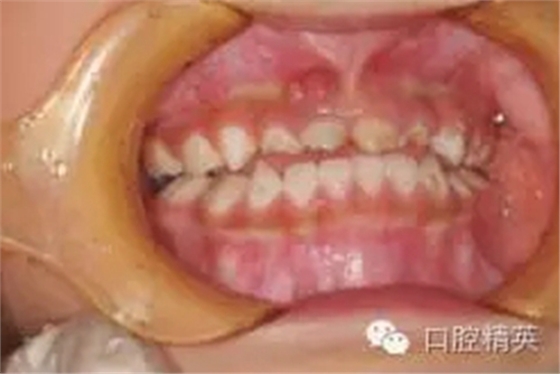

臨床檢查:頜面部及頸部未見明顯異常??谇恍l(wèi)生狀況尚可, 52,61,62,63,73唇舌面齲,54,64,74,84牙合面齲壞,腐質(zhì)中等,叩(-),松(-),牙齦未見明顯異常;75牙合面深齲壞,大量軟腐,叩(-),松(-),牙齦未見明顯異常,腐質(zhì)未去凈見露髓孔;51大面積齲壞,大量腐質(zhì),叩(+),松(Ⅰ),唇側(cè)牙齦可見5mm×6mm的包,軟;余牙未見異常。

診斷:S-ECC